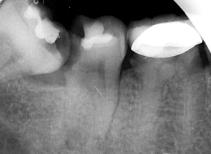

检查:全口卫生差,牙石++,软垢+,牙龈正常,有退缩。47牙远中合面龋坏,冷+,探-,叩+,松-.48牙近中阻生。 X线:47牙合面可见低密度暗影,累及髓腔,未行根管治疗。48牙近中阻生。

诊断:47牙急性牙髓炎;48牙阻生齿。 治疗计划:拔除阻生齿,并行47牙根管治疗。 治疗:拔除阻生齿后,阿替卡因局部浸润麻醉,47牙去净龋坏,开髓揭髓室顶,探查根管4根,牙髓摘除术,K锉初步预备,根管测长仪测量根管长度,各根管内导入根管润滑剂EDTA,protaper镍钛器械预备根管,冲洗,超声荡洗,水溶性氢氧化钙充填根管,暂封,约复诊。 复诊:一周后,诊间无不适,47

牙暂封完好,冷-,探-,叩-,不松。 试主尖,大锥度牙胶尖+AH-PLUS糊剂充填根管,热压充填牙胶,暂封。